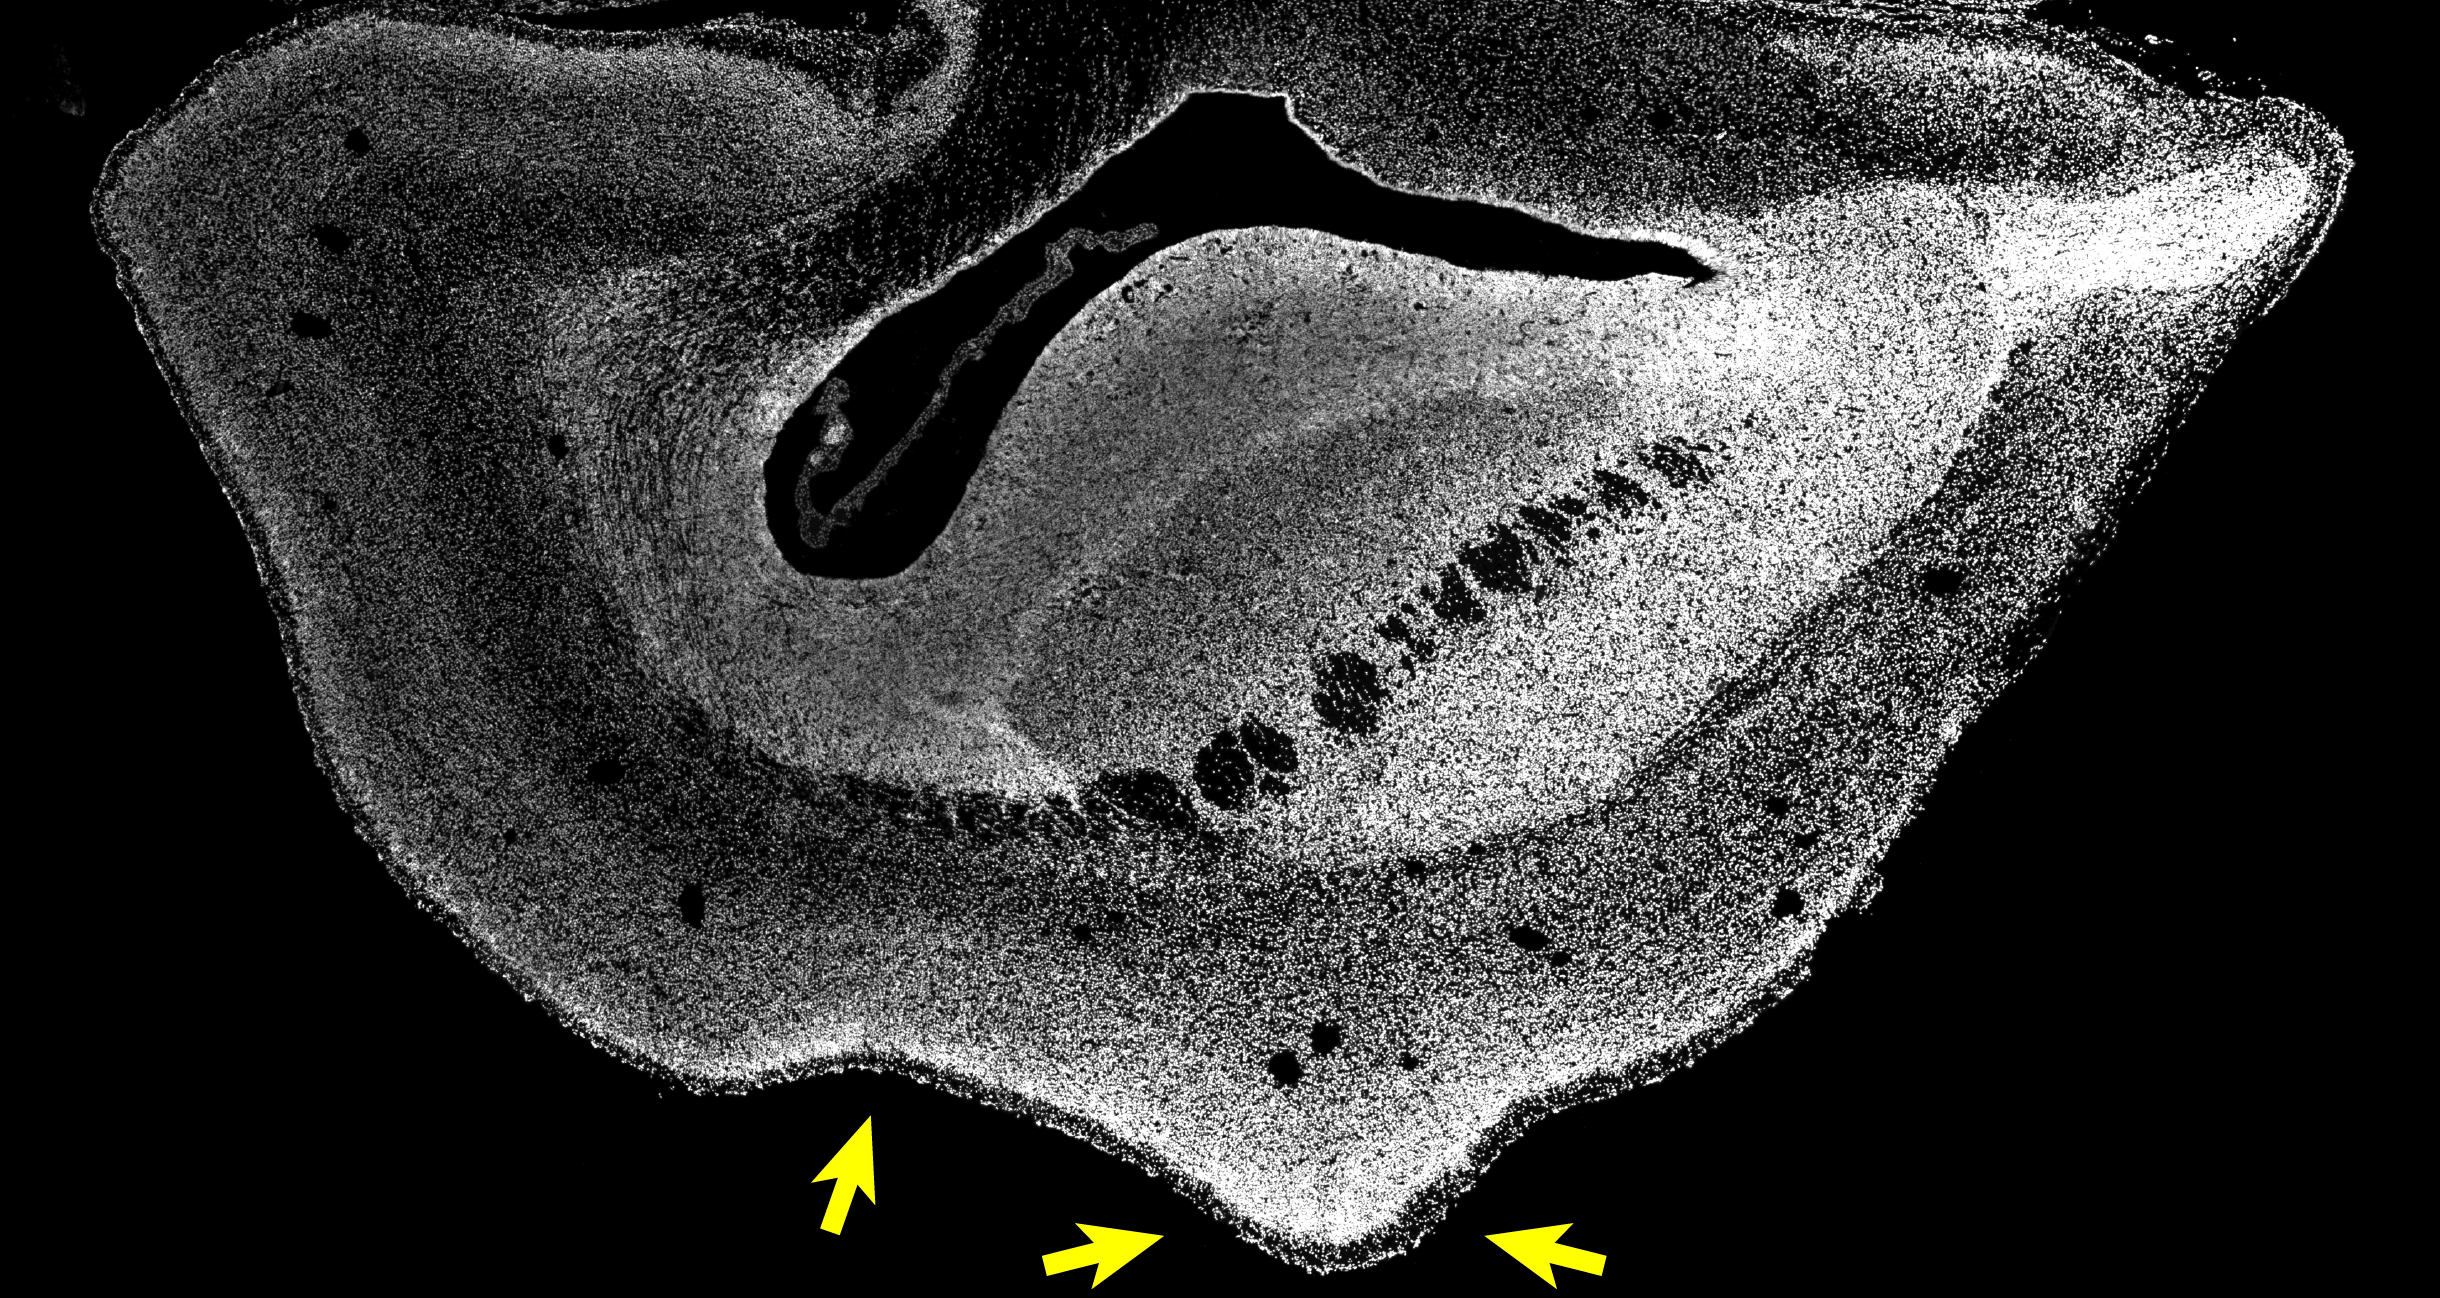

Bisher war jedoch ungeklärt, ob das menschenspezifische Gen ARHGAP11B auch bei nichtmenschlichen Primaten einen vergrößerten Neokortex verursachen würde. Um dies zu untersuchen, arbeiteten die Forscher in der Gruppe von Wieland Huttner mit Erika Sasaki am Zentralinstitut für Versuchstiere (CIEA) in Kawasaki und Hideyuki Okano an der Keio-Universität in Tokio, beide in Japan, zusammen. Diese japanischen Forscher sind Pioniere bei der Entwicklung einer Technologie zur Erzeugung transgener nichtmenschlicher Primaten. Der Erstautor der Studie, Postdoc Michael Heide, reiste nach Japan, um mit den Kollegen direkt vor Ort zusammenzuarbeiten. Gemeinsam erzeugten sie transgene Weißbüschelaffen (Neuweltaffen), die das menschenspezifische Gen ARHGAP11B im sich entwickelnden Neokortex exprimierten. Diese Affen haben dieses Gen normalerweise nicht. Japan hat ähnlich hohe ethische Standards und Vorschriften hinsichtlich Tierversuche und Tierschutz wie Deutschland. Die Gehirne von 101 Tage alten Föten des Weißbüschelaffen (50 Tage vor dem normalen Geburtsdatum) wurden in Japan gewonnen und zur detaillierten Analyse an das MPI-CBG in Dresden exportiert. Michael Heide erklärt: „Wir stellten in der Tat fest, dass der Neokortex des Gehirns der Weißbüschelaffen vergrößert und die Hirnoberfläche gefaltet war. Auch die sogenannte Kortikalplatte war dicker als normal. Darüber hinaus fanden wir eine höhere Anzahl bestimmter Vorläuferzellen, nämlich der basalen radialen Gliazellen, in der äußeren subventrikulären Zone, sowie eine höhere Anzahl von Neuronen in den oberen Schichten der Großhirnrinde. Letztere Neurone treten charakteristischerweise in der Primatenevolution vermehrt auf.“ Die Forscher hatten nun funktionelle Beweise dafür, dass ARHGAP11B eine Vergrößerung des Neokortex bei Primaten hervorrufen kann.